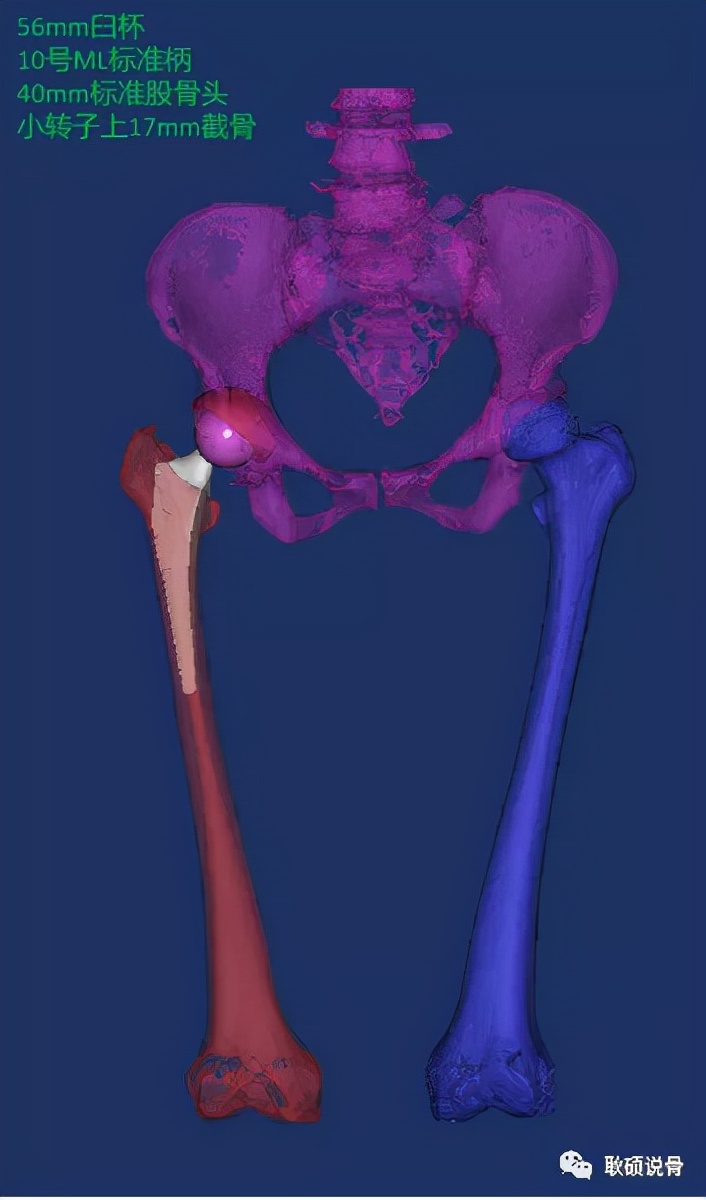

在孙女士入院后,凭借着哈医大一院数字骨科的诊疗优势,我们对孙女士的髋部情况进行了髋关节的三维CT扫描,并进行了三维重建。对于这种终末期的股骨头坏死,一些保髋术式如髓芯减压、截骨术已经不再适用,而关节置换是直接解决疼痛和改善髋关节功能的有效方法,因孙姐较年轻,关节假体在医生的讲解下选择了较耐磨的“陶瓷对陶瓷”摩擦界面。在关节外科领域有句话叫做:如果你没有术前计划,那么你就在计划失败。所以精准的术前计划必不可少。借助术前规划技术,我们测量孙女士的解剖参数来了解其髋关节解剖特点,通过关节假体的模拟安装来确定臼杯的大小、股骨柄的类型和大小、截骨的高度等信息。